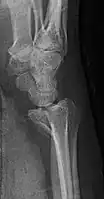

Lateral projectional radiograph of the same fracture -